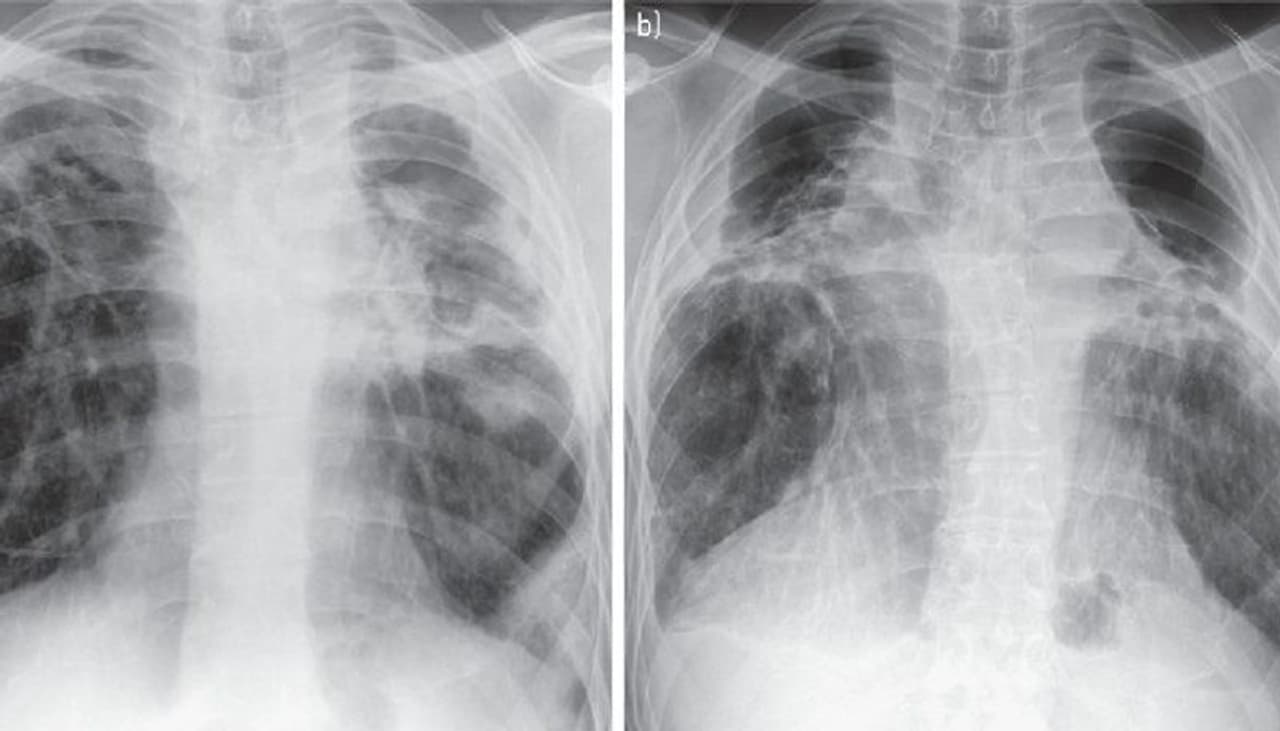

ബ്ലാക്ക് ഫംഗസ് ബാധയുടെ ലക്ഷണങ്ങളോട് സാമ്യതയുള്ള ലക്ഷണങ്ങള് തന്നെയാണേ്രത ഗ്രീന് ഫംഗസിലും കാണപ്പെടുന്നത്. എന്നാല് ബ്ലാക്ക് ഫംഗസിനോളം ഇതിനെ ഭയപ്പെടേണ്ടതില്ലെന്നും വിദഗ്ധര് പറയുന്നു. സാധാരണനിലയില് ആരോഗ്യമുള്ള വ്യക്തികളും മറ്റ് അസുഖങ്ങളില്ലാത്തവരും എല്ലാം തന്നെ ശ്വസനത്തിലൂടെ അകത്തെടുക്കാന് സാധ്യതയുള്ള ഫംഗസാണ് ഇതും. എന്നാല് പ്രതിരോധശേഷി കുറഞ്ഞിരിക്കുന്നവരില് ശ്വാസകോശത്തില് അണുബാധയുണ്ടാവുകയാണ്. നേരത്തേ തന്നെ ശ്വാസകോശ രോഗമുള്ളവരിലും 'ആസ്പെര്ജിലോസിസ്' പിടിപെടാന് സാധ്യതയുണ്ട്.